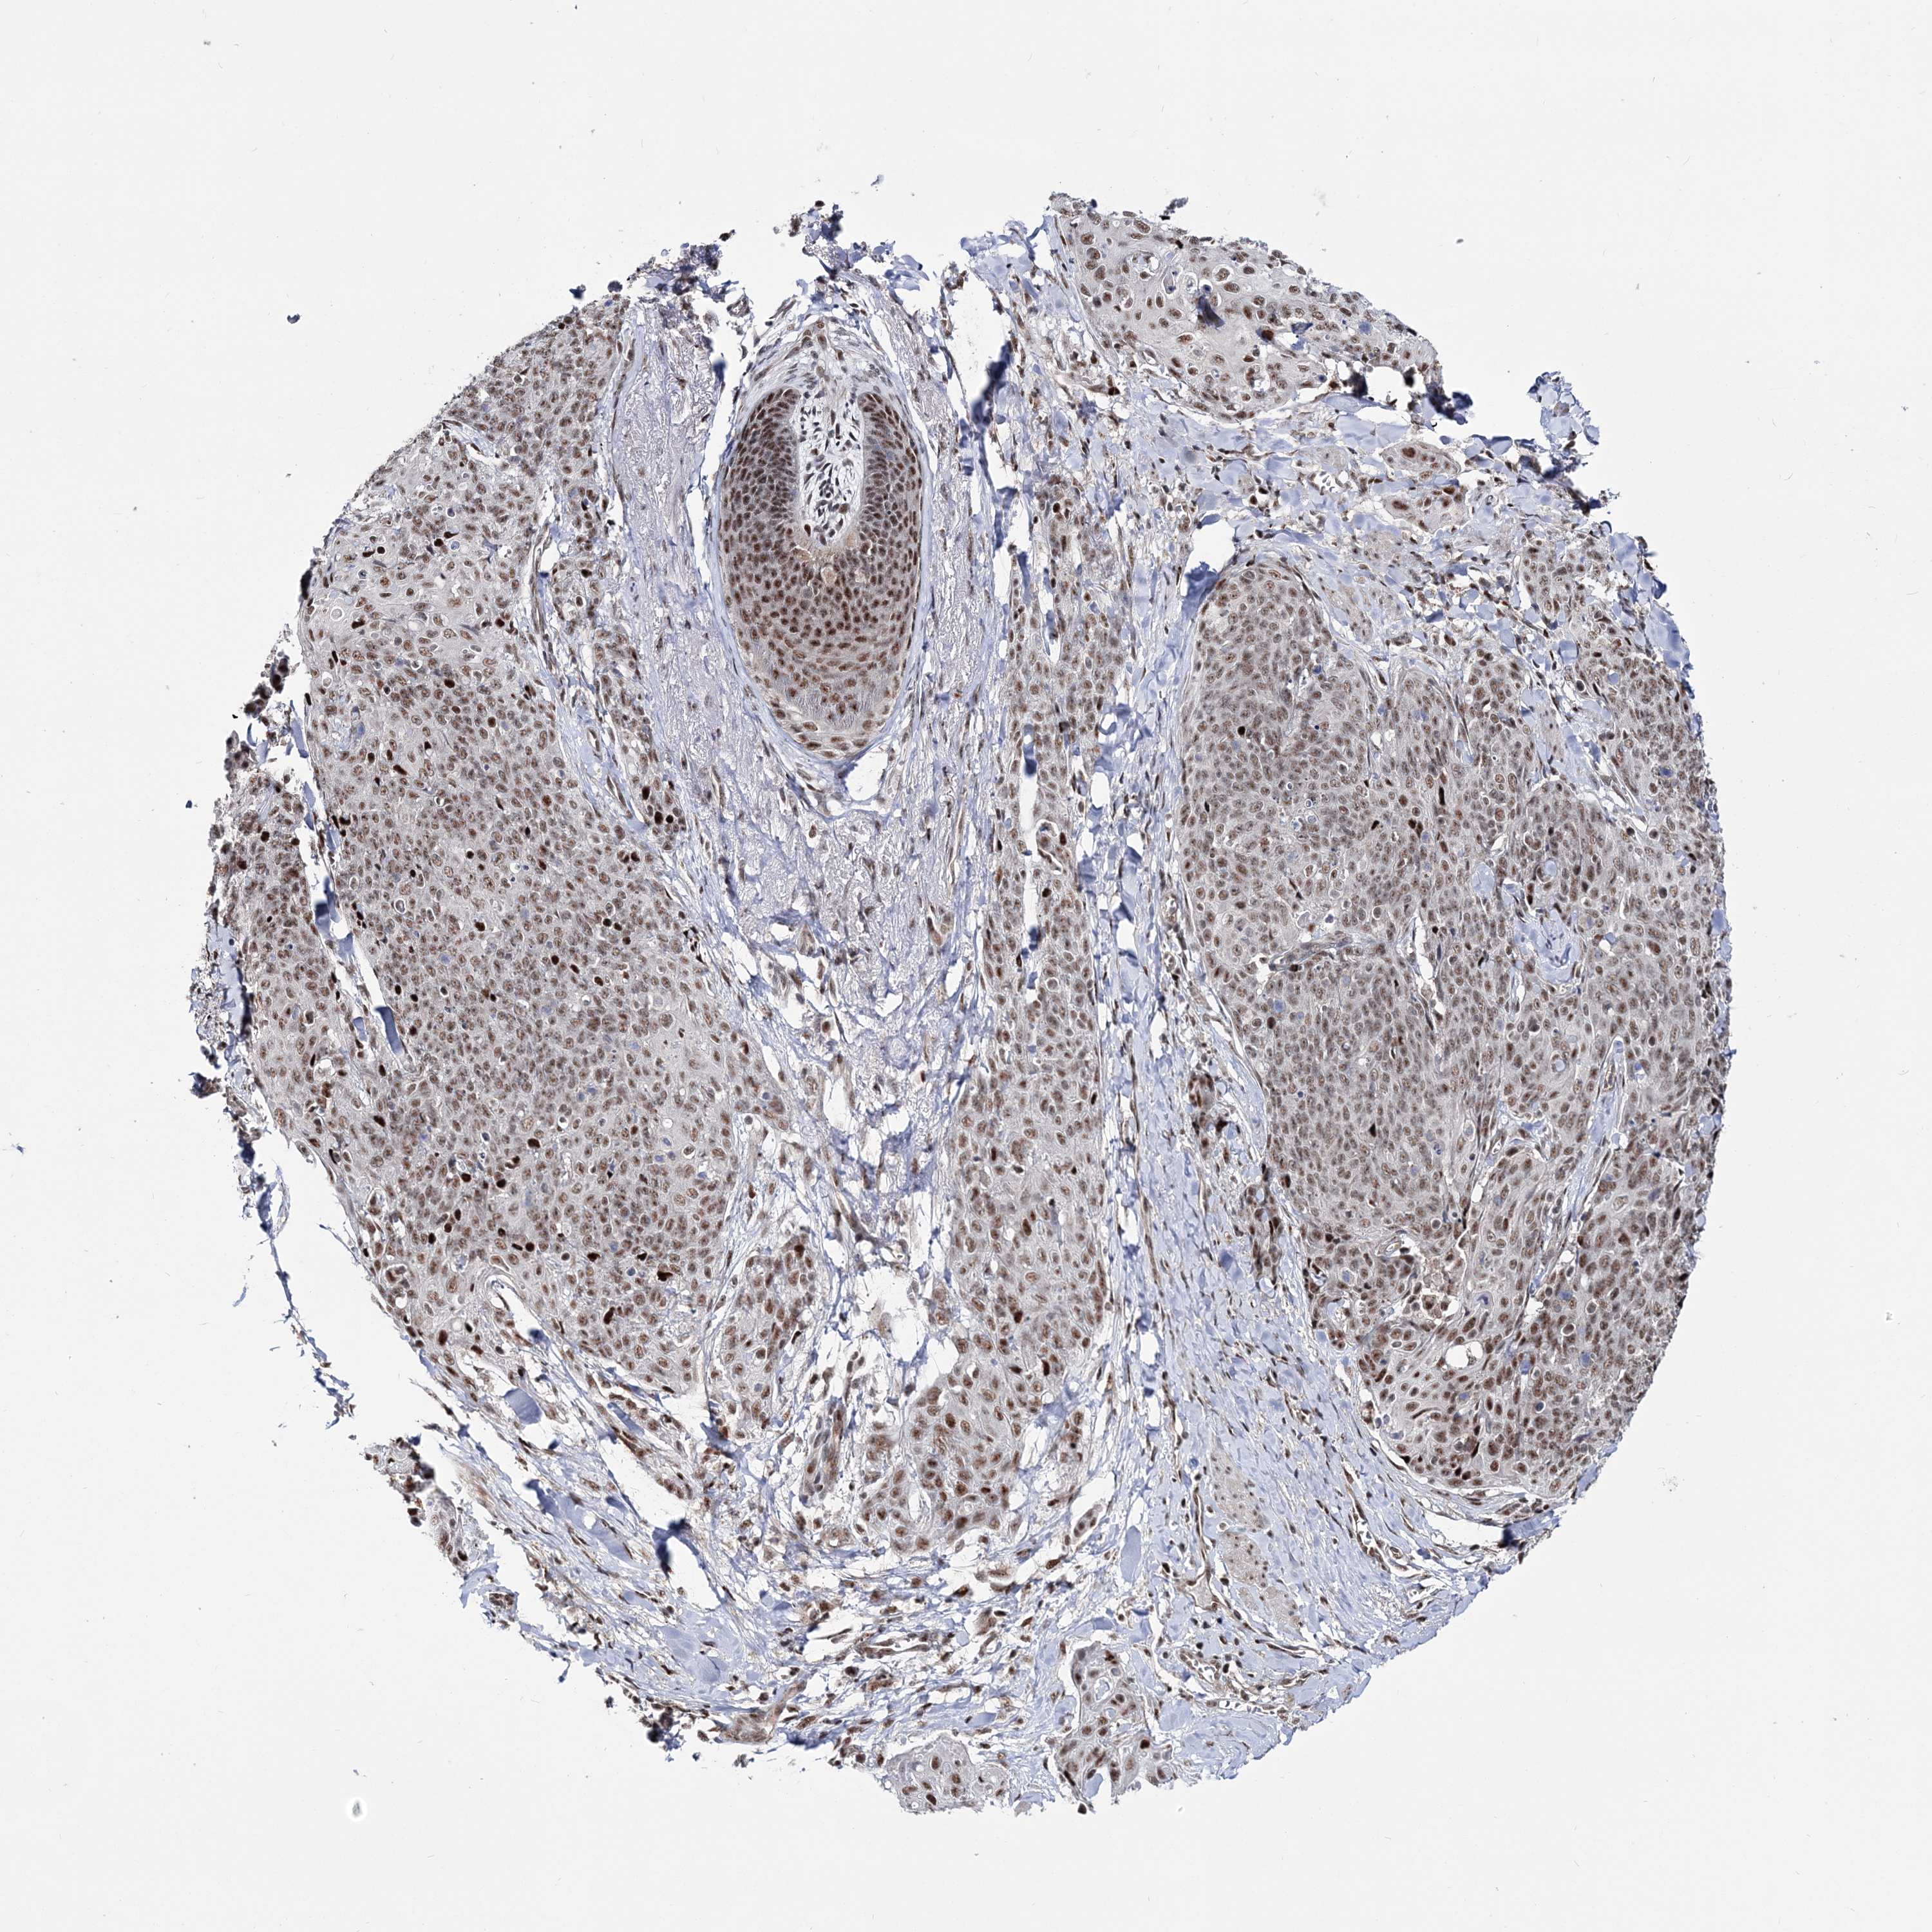

SKIN CANCER - Protein expressioni

A mouse-over function shows sample information and annotation data. Click on an image to view it in a full screen mode. Samples can be filtered based on level of antibody staining by selecting one or several of the following categories: high, medium, low and not detected. The assay and annotation is described here.

Antibody stainingi

Antibody staining in the annotated cell types in the current human tissue is reported as not detected, low, medium, or high, based on conventional immunohistochemistry profiling in selected tissues. This score is based on the combination of the staining intensity and fraction of stained cells.

Each image is clickable and will lead to virtual microscopy that enables deeper exploration of all samples and also displays staining intensity scores, fraction scores and subcellular localization as well as patient and tissue information for each sample.

Antibody HPA036822

Staining

High

Medium

Low

Not detected

Intensity

Strong

Moderate

Weak

Negative

Quantity

>75%

75%-25%

<25%

None

Location

Nuclear

Cytoplasmic/membranous

Cytoplasmic/membranous,nuclear

Squamous cell carcinoma, NOS

Squamous cell carcinoma, metastatic, NOS